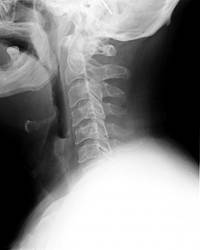

第三步:X光脊椎照片诊断

脊医会观察脊椎X光片各椎间的变化,脊柱轴线变异情况,椎体后缘联线变异情况。脊椎错位时会出现的仰位、倾位、仰旋、倾旋和侧旋等改变。各椎间关节形态或位移都属颈椎关节错位的表现。观察各椎间盘变性、椎间关节骨质增生,各韧带钙化的部位、程度等。并与第一、二步定位诊断结合分析,作出最后的诊断结果。

X光脊椎照片诊断的重要性:

1、排除脊柱肿瘤、结核、骨折、脱位及类风湿、痛风等病症。

2、分析椎间关节错位的部位及方向。

3、分析椎间盘变化程度,骨质增生部位与症状部位的关系。